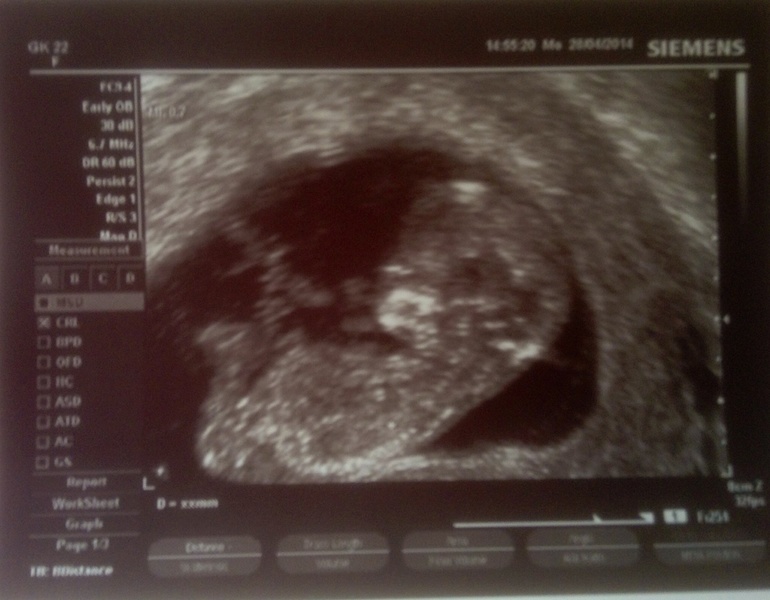

И сегодня мы познакомились с пилотом поближе.

Мы сегодня ходили вставать на учет. Врача на участке у нас нет, и после больницы всех принимает заведующий. Посмотрел он на нас, пожурил за поздний учет, но, увидев, что у нас уже и анализы сданы, и два узи было, вздохнул, да и договорился на скрининг на сегодня.

Узистка совершено чудесная, я начинаю верить во врачей... Трогательно называла малыша пупсом и просила повернуться как надо. Папе нашему объясняла все и показывала. Мне видно не было, показывали мало что, приходилось довольствоваться горящими глазюками мужа.

Больше всего восхитила чудесная маленькая лапка. Пять крохотулечных пальчиков, чудесная пяточка...! Он маленький такой, а у него есть эта мяконькая пятка!

По УЗИ у нас все хорошо. ТВП 1,1, носовая косточка четко визуализируется. Мылыш сначала активно кувыркался, потом успокоился, закрыл лицо ручками и долго не давал рассмотреть носик.

У нас, кажется, мальчик. Врач говорит, что сомнений практически нет. Муж поддакивает, говорит что там тааак все торчааало... :)

В общем, 11 недель и два дня, полет нормальный!